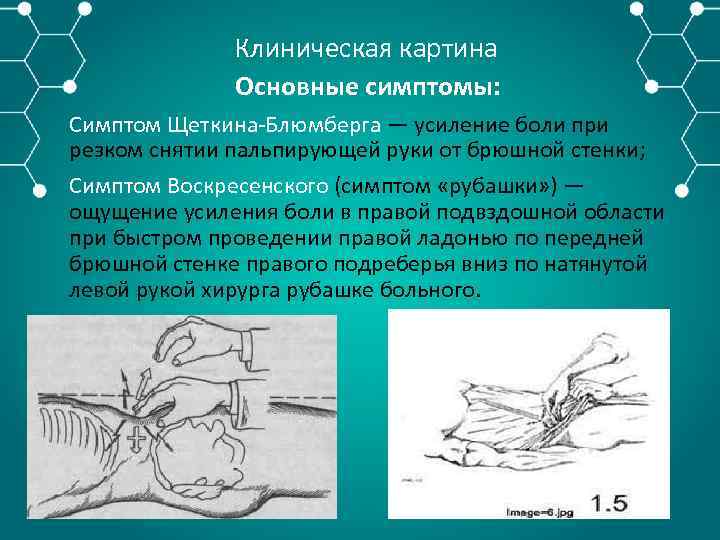

Клиническая картина Основные симптомы: Симптом Щеткина Блюмберга — усиление боли при резком снятии пальпирующей руки от брюшной стенки; Симптом Воскресенского (симптом «рубашки» ) — ощущение усиления боли в правой подвздошной области при быстром проведении правой ладонью по передней брюшной стенке правого подреберья вниз по натянутой левой рукой хирурга рубашке больного.